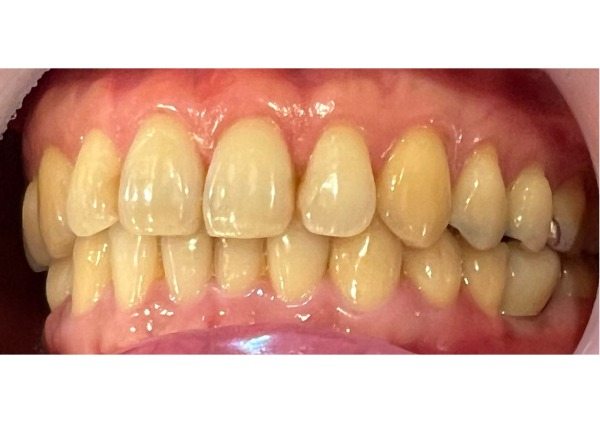

13日目 被せ物を装着しました。

治療後の様子

患者様はこれまでの歯科医院で、エックス線検査を受け、「もう抜歯しかない」と言われていましたが、何とか残す方法がないかと自分の歯の保存を希望されていました。当院にて、エックス線検査、CT検査、口腔内カメラで多角的に調べることができ、詳しい検査がとても大事だと感じたそうです。

「1つひとつの検査を行う意味を段階的に説明していただいたので、わかりやすく、非常に良かった」と満足されていました。

また、破折した歯の写真を実際に確認したことで抜歯しかないと受け入れることができ、インプラント治療を受けようと前向きに決断できたとのことでした。